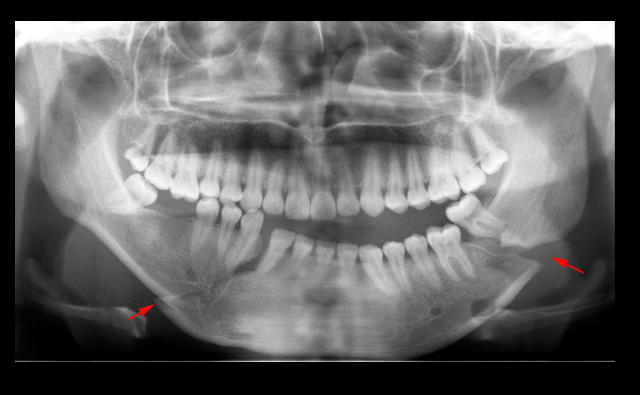

Al llegar al hospital los médicos lo ingresaron rápidamente a cirugía, donde trabajaron para reconstruir y reparar el hueso fracturado.